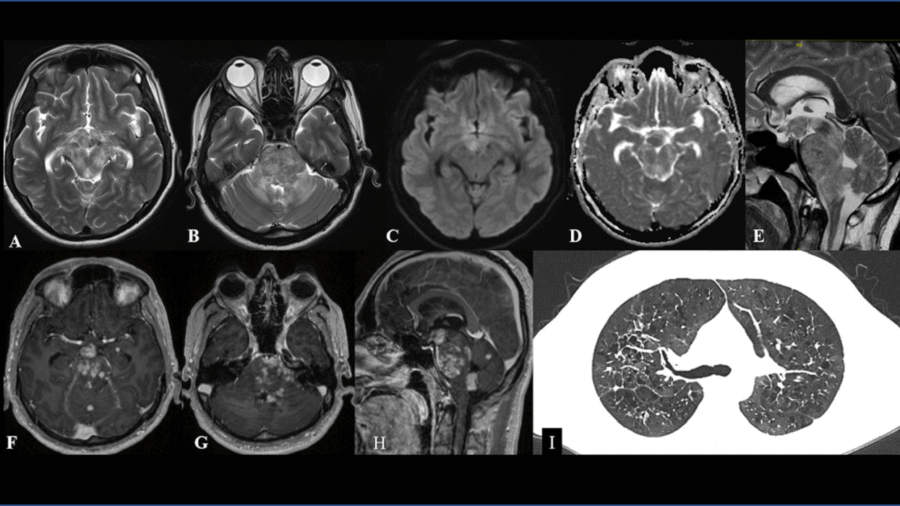

A 21 year old male was brought for evaluation of fever since 45 days associated with holocranial headache for 30 days and altered sensorium for 20 days . Working clinical diagnosis of chronic meningoencephalitis was made for which cross sectional imaging was requested.